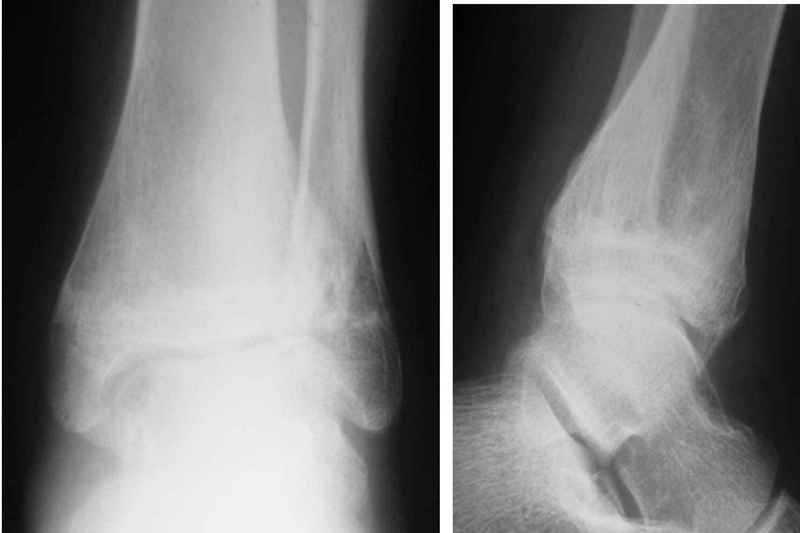

Здравствуйте, коллеги.Обратились родители мальчика 15 лет. Сами врачи.В июле 2009 года - перелом лодыжек.

Лечили спорно, на мой взгляд. В результате - - сращение наружной лодыжки с укорочением, подвывих голеностопа кнаружи (вальгус) в итоге компенсаторно передний отдел стопы ставит на варус. Нагрузку ограничивает.

Снимки в приложении.